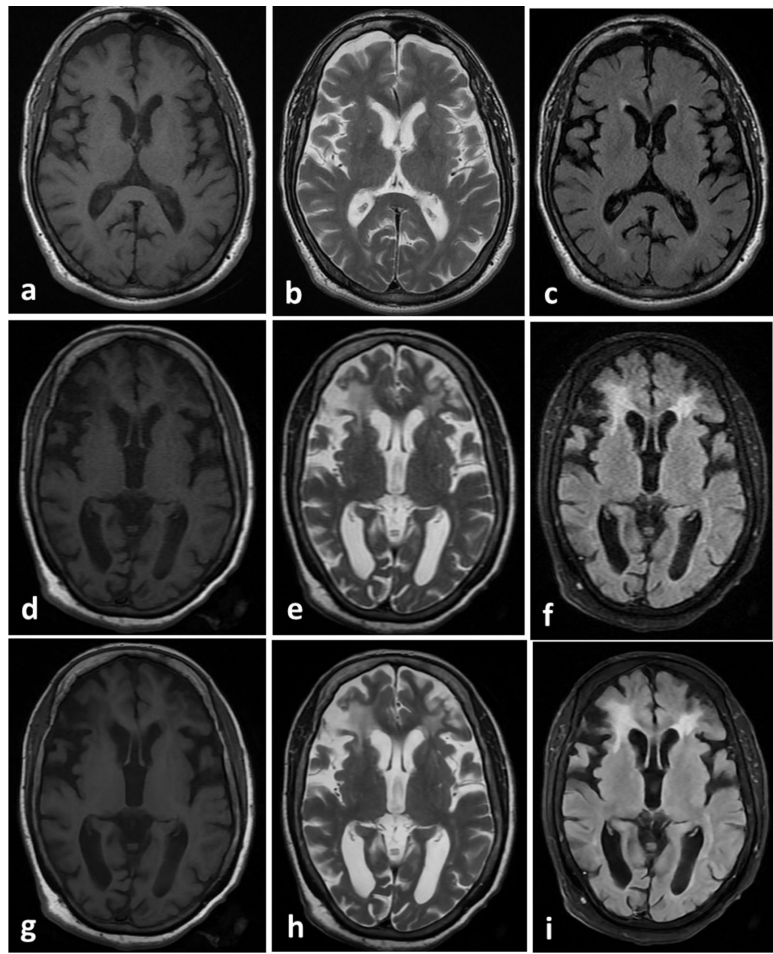

典型病例对比

如图2所示,60岁正常受试者的DL重建T1、T2、FLAIR图像,在保留全部解剖细节的同时,白质-灰质对比度明显增强。更令人惊喜的是图3展示的66岁脑缺血患者案例,DL重建不仅清晰显示脑沟增宽和脑室旁慢性缺血灶,还改善了传统MRI常见的脑脊液搏动伪影。